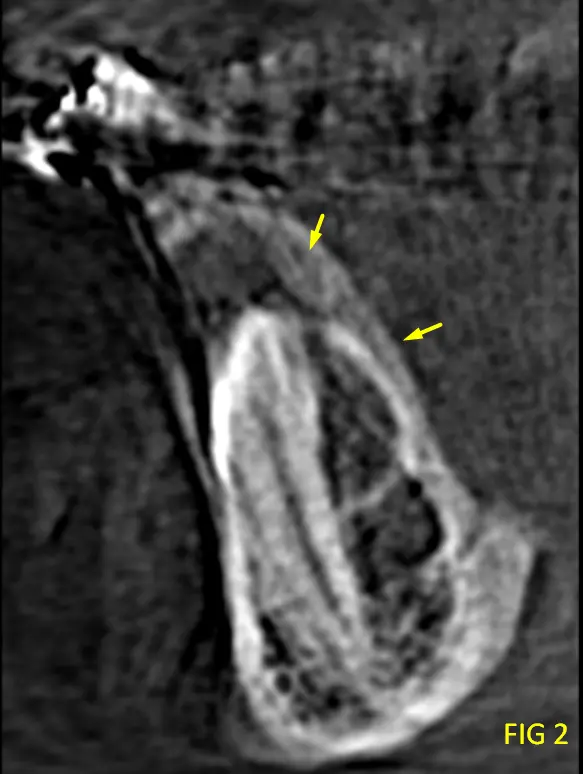

Paciente con ortodoncia, poco colaborativo (se movia) y que ademas presentaba ortodoncia, lo que dificulta obtener una imagen de buena calidad (Imagen 3D). Durante la evaluación de la tomografía se visualiza una pieza dentaria no erupcionada (PD 41 ) que presentaba en boca todavia su PD temporaria 81, esa pieza dentaria presentaba un saco dentinario aumentado de tamañao lo que nos lleva al diagnóstivo presuntivo de un Quiste Dentígero, pero además se observa que en el mismo se observa un pequeño elemento radiopaco asociada a dicha lesión, se identifica una imagen hiperdensa, de morfología irregular, compatible con un quiste dentario organizado, correspondiente a un odontoma (ver cortes coronal, axial, transaxial, Fig 1, 2 y 3).

Las características imagenológicas nombradas son compatibles con Quiste dentígero de Pd 41 asociado a un odontoma compuesto.